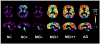

Imaging agents capable of assessing amyloid-beta (Abeta) content in vivo in the brains of Alzheimer's disease (AD) subjects likely will be important as diagnostic agents to detect Abeta plaques in the brain as well as to help test the amyloid cascade hypothesis of AD and as an aid to assess the efficacy of anti-amyloid therapeutics currently under development and in clinical trials. Positron emission tomography (PET) imaging studies of amyloid deposition in human subjects with several Abeta imaging agents are currently underway. We reported the first PET studies of the carbon 11-labeled thioflavin-T derivative Pittsburgh Compound B in 2004, and this work has subsequently been extended to include a variety of subject groups, including AD patients, mild cognitive impairment patients and healthy controls. The ability to quantify regional Abeta plaque load in the brains of living human subjects has provided a means to begin to apply this technology as a diagnostic agent to detect regional concentrations of Abeta plaques and as a surrogate marker of therapeutic efficacy in anti-amyloid drug trials.